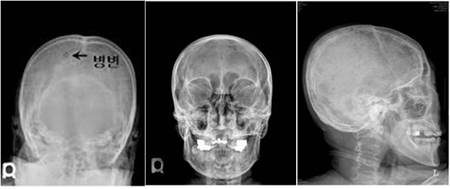

[ 다발골수종 환자의 두개골 X선 ]

다발골수종의 진단을 위해서는 혈액 및 소변 검사와 함께 골수검사를 시행하여 혈액 및 소변에서 검출되는 비정상 단클론단백(M 단백)의 확인과 함께 골수 내 클론성 형질세포를 확인하게 됩니다. 채취된 골수를 통해 다발골수종의 진단뿐만 아니라 염색체와 유전자 검사를 시행하여 향후 질환의 경과 및 예후에 대한 정보를 얻을 수 있습니다. 또한 단순 방사선 검사(X-ray) 및 전산화 단층 촬영(CT)이나 자기공명영상(MRI)와 같은 영상학적 검사를 통해 종양이 발견되는 경우 조직 검사를 통해 진단하기도 합니다.

다발골수종 환자의 가장 흔한 증상은 허리 통증이나 갈비뼈의 통증입니다. 이 통증은 파골세포(osteoclast)가 뼈 조직을 파괴하여 생기는데 안정 시에는 경미하지만 움직일 때는 통증이 심하고 아픈 부위가 이동하는 것이 특징입니다. 통증이 계속되면 병적 골절의 가능성도 염두에 두어야 합니다. 또 뼈 조직이 파괴되어 칼슘이 혈액으로 과도하게 방출되면 심한 고칼슘 혈증이 일어납니다. 칼슘 농도가 높아지면서 심각한 탈수, 피로, 무력감, 입맛의 소실, 구갈, 의식 저하 등의 현상이 나타날 수 있고, 심장 및 신장에 피해를 줄 수 있습니다.